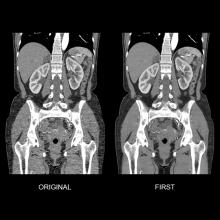

This is an example of Canon's Advanced intelligent Clear-IQ Engine (AiCE) AI-driven image reconstruction software that is now being used to improve image quality on the Canon Celesteion Prime PET/CT nuclear imaging system. The deep learning is used to enhance the iterative reconstruction used to reduce noise and sharped high contrast resolution on positron emission tomography (PET) images from the digital PET detector used on the system.

This example is a whole-body FGD PET scan of a patient with a large BMI with lung cancer.

The Cartesion Prime PET/CT is the industry’s only air-cooled digital PET/CT, provides variable bed time (vBT) acquisition as a standard feature. This and the new FDA 510(k)-pending AiCE technology were highlighted at the 2020 Radiological Society of North America (RSNA) virtual meeting.